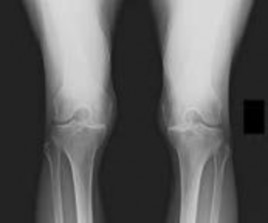

Question 11:

A 14-year-old female presents for operative evaluation of adolescent idiopathic scoliosis. Standing full-length spine radiographs show a main thoracic curve of 55 degrees and a lumbar curve of 35 degrees. The proximal thoracic curve is 20 degrees. On side-bending radiographs, the main thoracic curve corrects to 30 degrees, the lumbar curve corrects to 15 degrees, and the proximal thoracic curve corrects to 5 degrees. Based on the Lenke classification, what is the correct curve type?

Options:

- Type 1 (Main Thoracic)

- Type 2 (Double Thoracic)

- Type 3 (Double Major)

- Type 4 (Triple Major)

- Type 5 (Thoracolumbar/Lumbar)

Correct Answer: Type 1 (Main Thoracic)

Explanation:

In the Lenke classification system, a curve is considered structural if it fails to correct to < 25 degrees on side-bending radiographs or has an associated regional kyphosis > +20 degrees. Here, the lumbar curve corrects to 15 degrees (non-structural) and the proximal thoracic corrects to 5 degrees (non-structural). The main thoracic curve is the major curve (largest magnitude, 55 degrees). A major main thoracic curve with non-structural minor curves is classified as a Lenke Type 1.